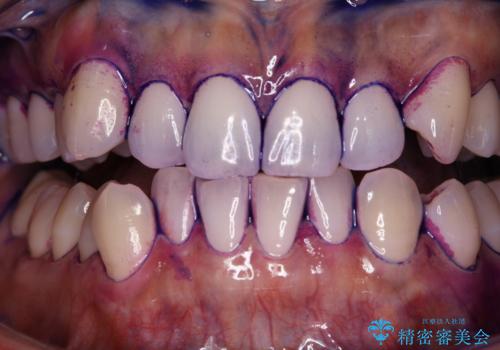

染め出しをしてエアフローで綺麗にクリーニング

染め出し液を使ってプラークを染め出すことにより、普段の歯みがきで磨き残している場所を目で確かめることができます。

エアフローワンは、特殊なパウダーを混ぜた水を水面にジェット噴射することでバイオフィルム(プラーク)・ステイン(着色)・早期歯石を天然歯やインプラント周囲から除去することが可能な歯面清掃器具です。